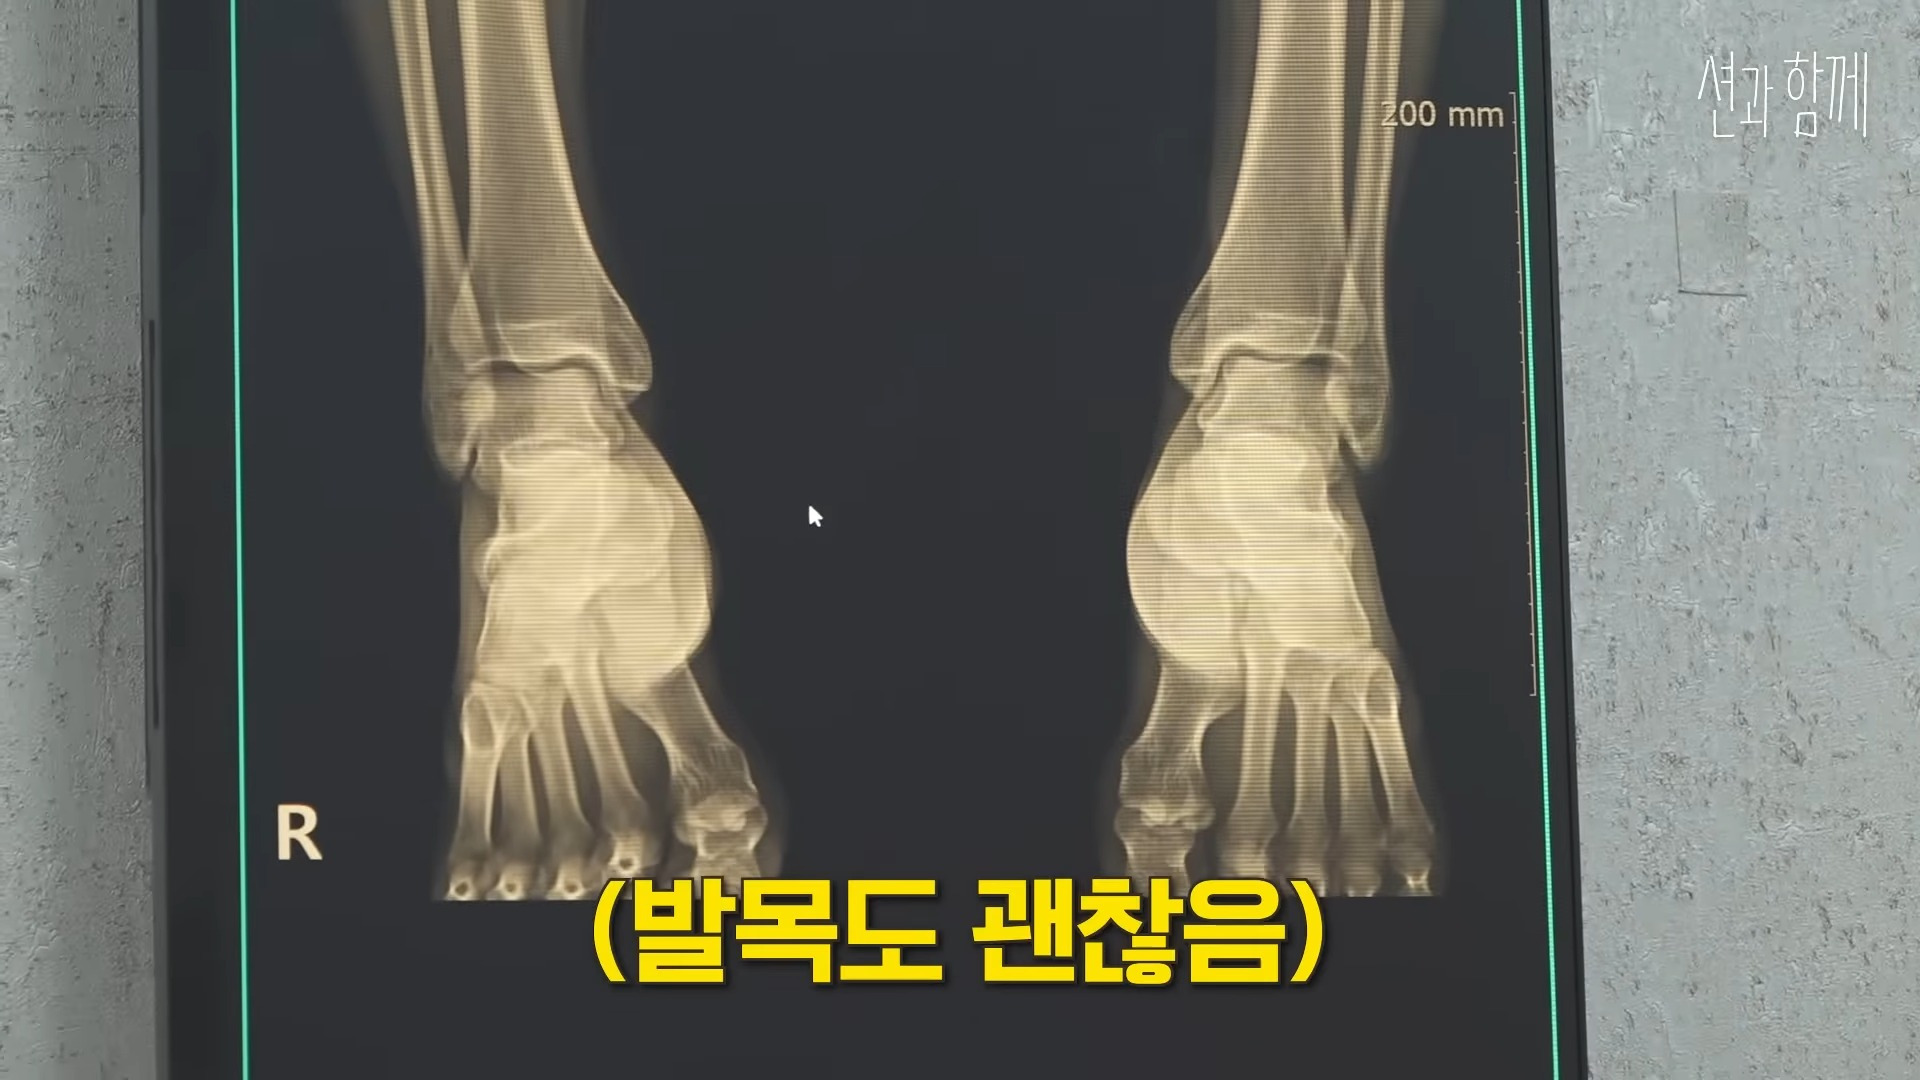

충격적인 션 건강상태

의사 피셜 기초대사량 정상으로 나오는 사람 100명중 10명도 안된다함

51세